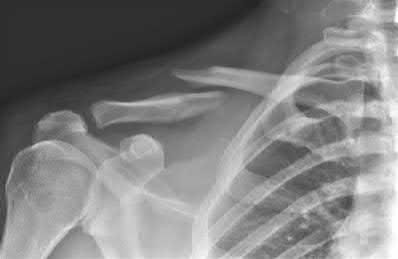

A 32-year-old female presents with a painless, slowly enlarging mass behind her knee. The radiograph is shown. Biopsy confirms a low-grade, bone-forming tumor on the surface of the posterior distal femur with a 'string sign' representing radiolucency between the tumor and the cortex. Which of the following genetic alterations is most classically associated with this diagnosis?

Options:

- t(11;22) chromosomal translocation

- t(X;18) chromosomal translocation

- GNAS gene mutation

- EXT1 gene mutation

- MDM2 and CDK4 gene amplification

Correct Answer: MDM2 and CDK4 gene amplification

Explanation:

The clinical scenario and imaging description represent parosteal osteosarcoma, a low-grade surface osteosarcoma typically found on the posterior aspect of the distal femur. It is characterized molecularly by ring chromosomes and amplification of the 12q13-15 region, which includes the MDM2 and CDK4 genes. t(11;22) is associated with Ewing sarcoma. t(X;18) is seen in synovial sarcoma. GNAS mutations are found in fibrous dysplasia. EXT1 mutations are associated with hereditary multiple exostoses.